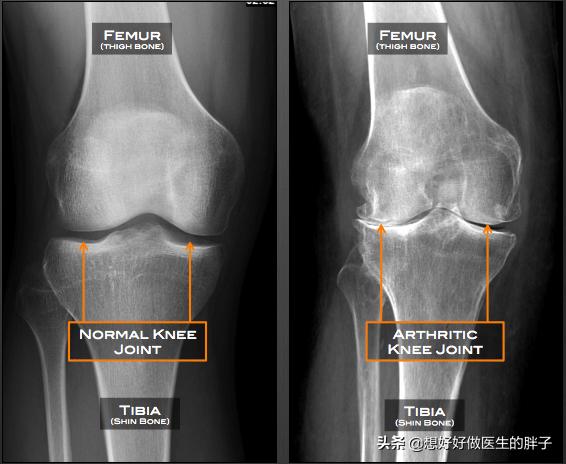

●膝関節のX線検査膝のレントゲンは、患者が著しい骨粗鬆症であるかどうか、関節腔に著しい狭窄があるかどうかを判断することができる。骨関節炎が存在するのだろうか?関節リウマチ。あるいは、他の一般的な膝の問題もある。

下の写真でわかるように、関節が発達しているのが典型的だ。目に見える隙間、狭い骨形成、より重い関節の骨粗鬆症。このような患者に明らかな異常感覚や痛みがある場合、硝酸ナトリウムの関節内注射や絶え間ない鎮痛剤の内服によって、患者は大きな痛みに苦しむことになるが、これは問題の解決にはあまり役立たない。

- 摩擦音--関節軟骨の磨耗がひどくなると、軟骨下骨の末端が軟骨の保護を失い、直接摩擦すると低くかすれた摩擦音を発します。関節腔内をさまよう軟骨の破片も詰まりやすく、関節摩擦音を発します。患者は正常な生理的ポッピングと区別する必要があり、判断基準は非常に簡単で、病的ポッピングはしばしば関節不快症状を伴う。